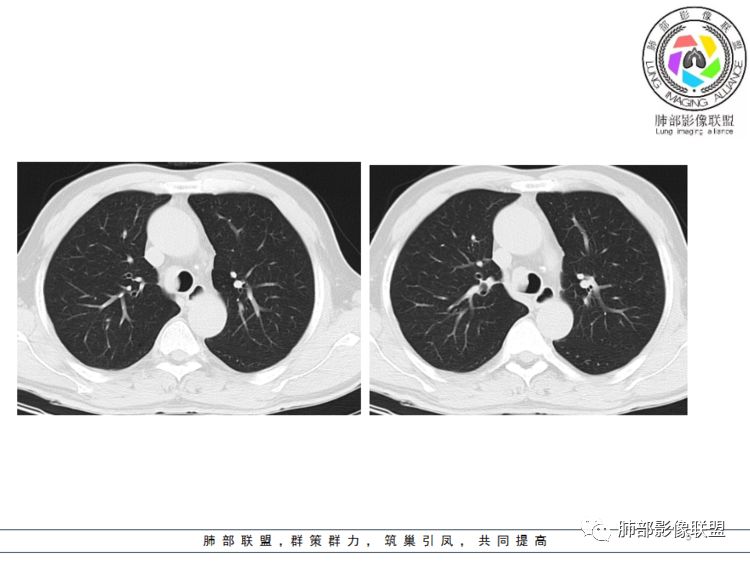

病灶跨气管壁内外,主体在外;边界清,密度均匀

明显看到气管壁软骨受压内移

局部是撑开的,就是说软骨不是破坏

表面隆起,有小斑点

无症状;倾向于良性,平滑肌瘤?神经源性肿瘤?不除外其他

南边分析:针对本例,病灶跨气管壁内外生长,常规跨内外的有:恶性肿瘤为主,其次就是神经源性、平滑肌瘤;常规的思维:跨内外就要看结构的变化气管的优势在于软骨相对密度高,而且成C型

我们如何分析这个病例?冠状位:软骨密度稍高;病灶区软骨部分区域不连续,外围连续,提示病灶推移为主,不是破坏为主;如果破坏,应该这些软骨显示不清,移位不明显

病灶从软骨见推移开,跨内外,因此定在良性。恶性是侵犯,破坏为主,如果破坏,应该这些软骨显示不清,移位不明显,不是推移为主这例病变定在良性,我们就要考虑:1、软骨之间的平滑肌来源;2、神经源性

病例小结      气管神经鞘瘤属于罕见的气管良性肿瘤,一般气管良性肿瘤或腔内或腔外生长的结节样改变,恶性肿瘤呈腔内外生长,但本例肿块向腔外生长,呈“冰山样改变”,即肿瘤的腔内部分较小而腔外部分较大,无周围组织侵犯。因此肿瘤腔内外生成不能作为鉴别气管良恶性肿块的绝对依据。        因此冠(矢)状位多平面观察、软骨是否破坏、气管壁有无增厚等细节观察,对于鉴别气管肿块良恶性有重要的参考性。

1.气管隆凸上右前壁不规则结节影,部分突入腔内,南边老师观察有推挤软骨环“破土而出”的形态特征。注意没有沿气管粘膜表面生长蔓延的生物学行为。

2.影像学病灶占据腔内外,但病灶边缘十分清楚。这点倾向良性。